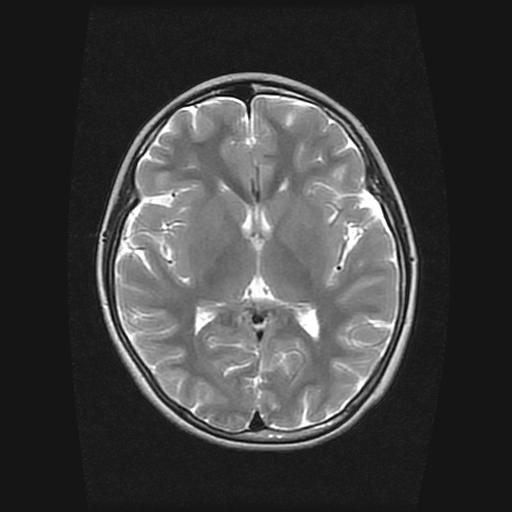

9岁女孩,三岁时诊断为癫痫,一直服丙戊酸钠,现患者一般情况良好,家长复查核磁片,看能否停药..

巨脑回